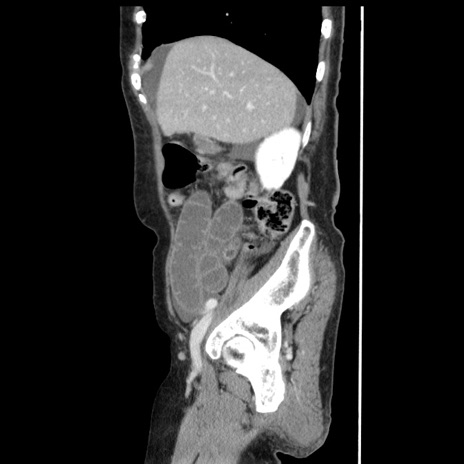

横断像

【症例】80歳代女性

【主訴】腹痛

【現病歴】8時間前から腹痛あり来院。

【既往歴】糖尿病、脂質異常症、子宮体癌にて子宮全摘術

【身体所見】意識清明・会話良好だが腹痛で苦悶様、全腹部にわたって反跳痛と圧痛あり

【データ】WBC 13600、CRP 0.14、LDH 224、CK 90